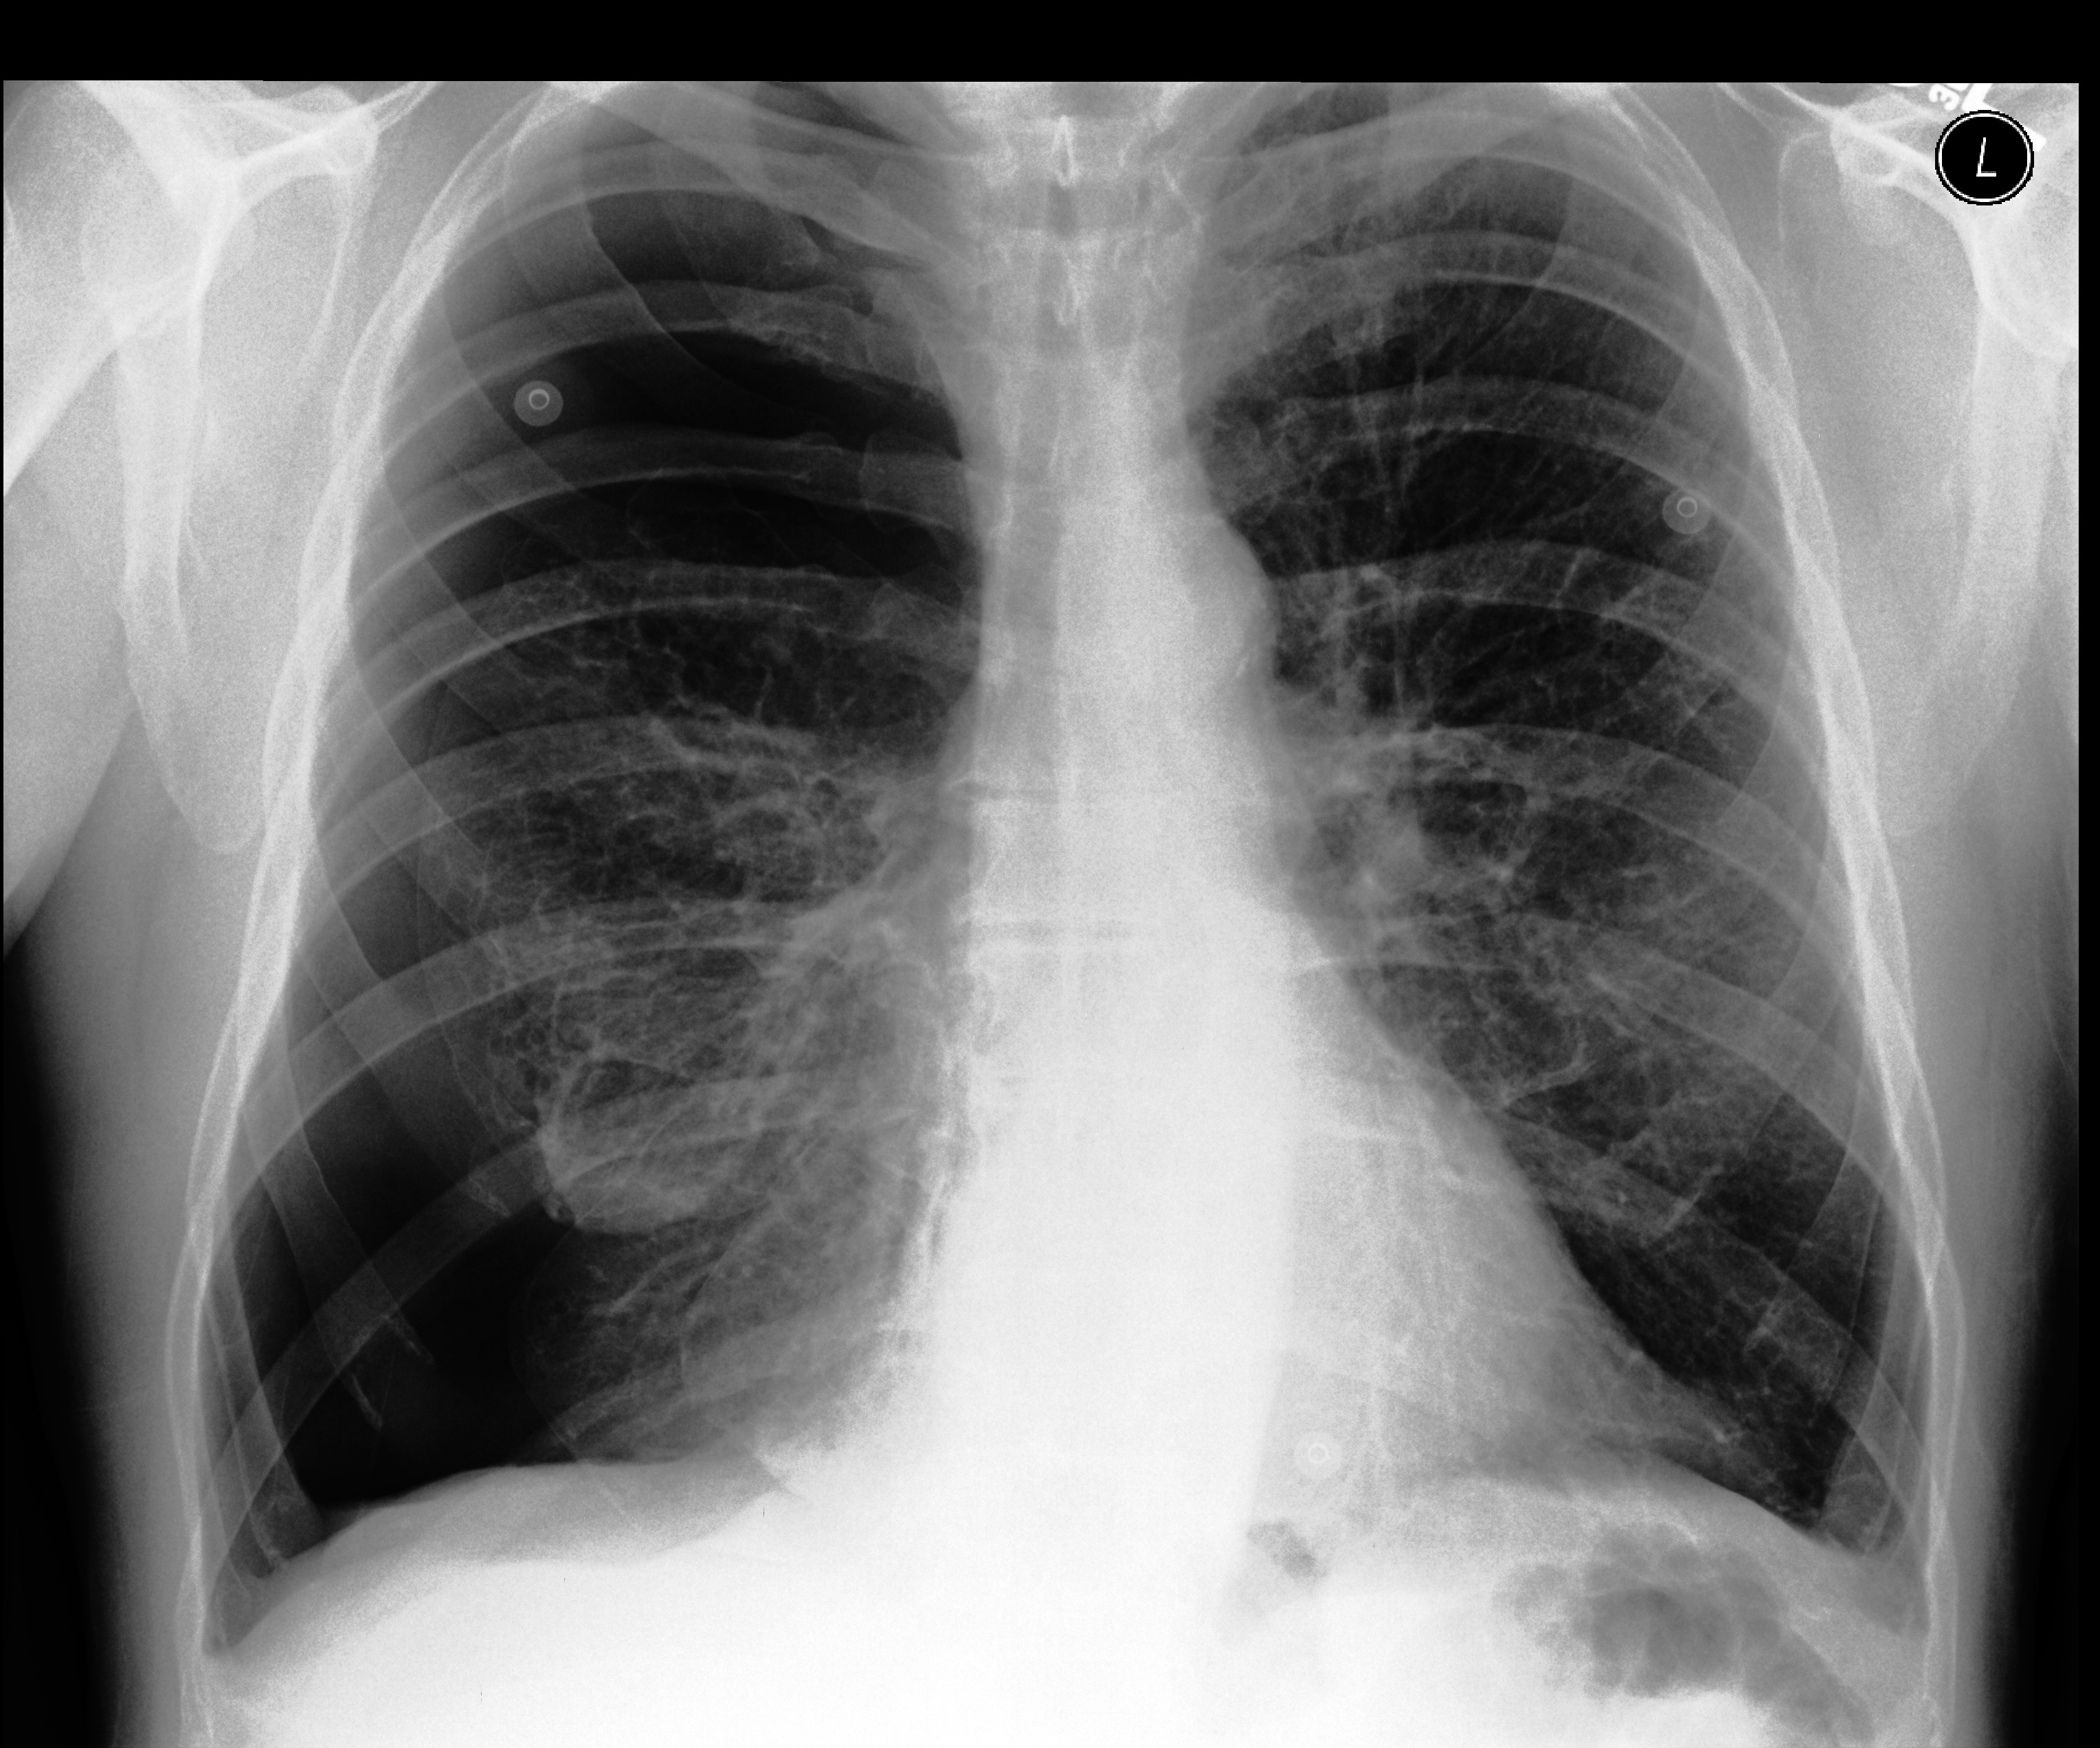

Table 1: Sample chest X-ray (CXR) images. The top row shows a normal CXR, while the remaining rows display CXRs with various pathologies, including right-sided cardiomegaly, large pneumothorax, viral pneumonia, and pulmonary edema.

Normal Chest X-ray Image

[Uncaptioned image]

Right-sided Cardiomegaly Large Pneumothorax

[Uncaptioned image] [Uncaptioned image]

Virus Pneumonia Pulmonary Edema